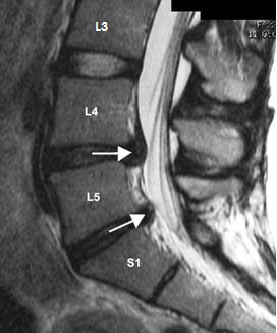

3.3 Comparing fat percentage between pre-training and post-training sessions

The MR images of two patients with lower back pain were acquired prior to and after completion of the physical training sessions prescribed by the physicians. The MR images captured at the lumbar disc positions (L3-L4-L5-S1), as shown in Figure 12, were considered for analysis using the tool. Even slight variations in the fat percentage of lumbar muscles between pre-training and post-training session could be easily identified using the tool, which were useful in determining the effectiveness of the training sessions. Tables 5 and 6 show the variations of fat percentage between pre-training and post-training session of patient I and patient II.

Refer to caption

Figure 12: Sagittal View of Lumbar Spine MRI showing spinal disc positions